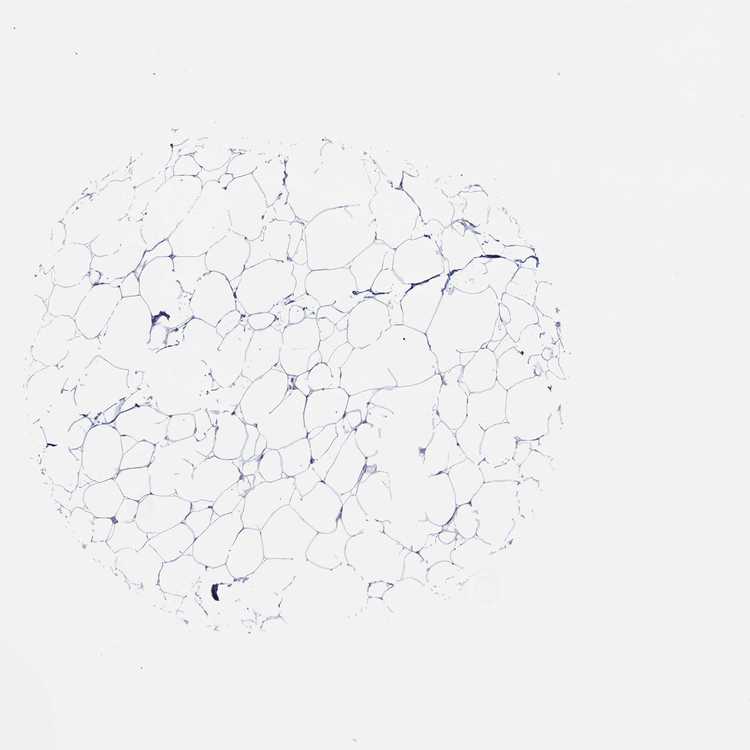

BREAST - Antibody stainingi

Antibody staining in the annotated cell types in the current human tissue is reported as not detected, low, medium, or high, based on conventional immunohistochemistry profiling in selected tissues. This score is based on the combination of the staining intensity and fraction of stained cells.

Each image is clickable and will lead to virtual microscopy that enables deeper exploration of all samples and also displays staining intensity scores, fraction scores and subcellular localization as well as patient and tissue information for each sample.

Antibody HPA005633Antibody CAB024847

Adipocytes Not detectedNot detected

Glandular cells MediumNot detected

Myoepithelial cells Not detectedNot detected